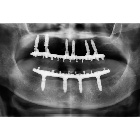

利用4-6顆植體及類似造橋的力學設計原理,將力量平均分配,使得傳統需要8-10顆植體才能支持的整排假牙,現在只須4-6顆植體即可達成。而且手術時間短,復原快速,如植體穩定性高,幾天之內患者就能恢復正常咀嚼。

圖2